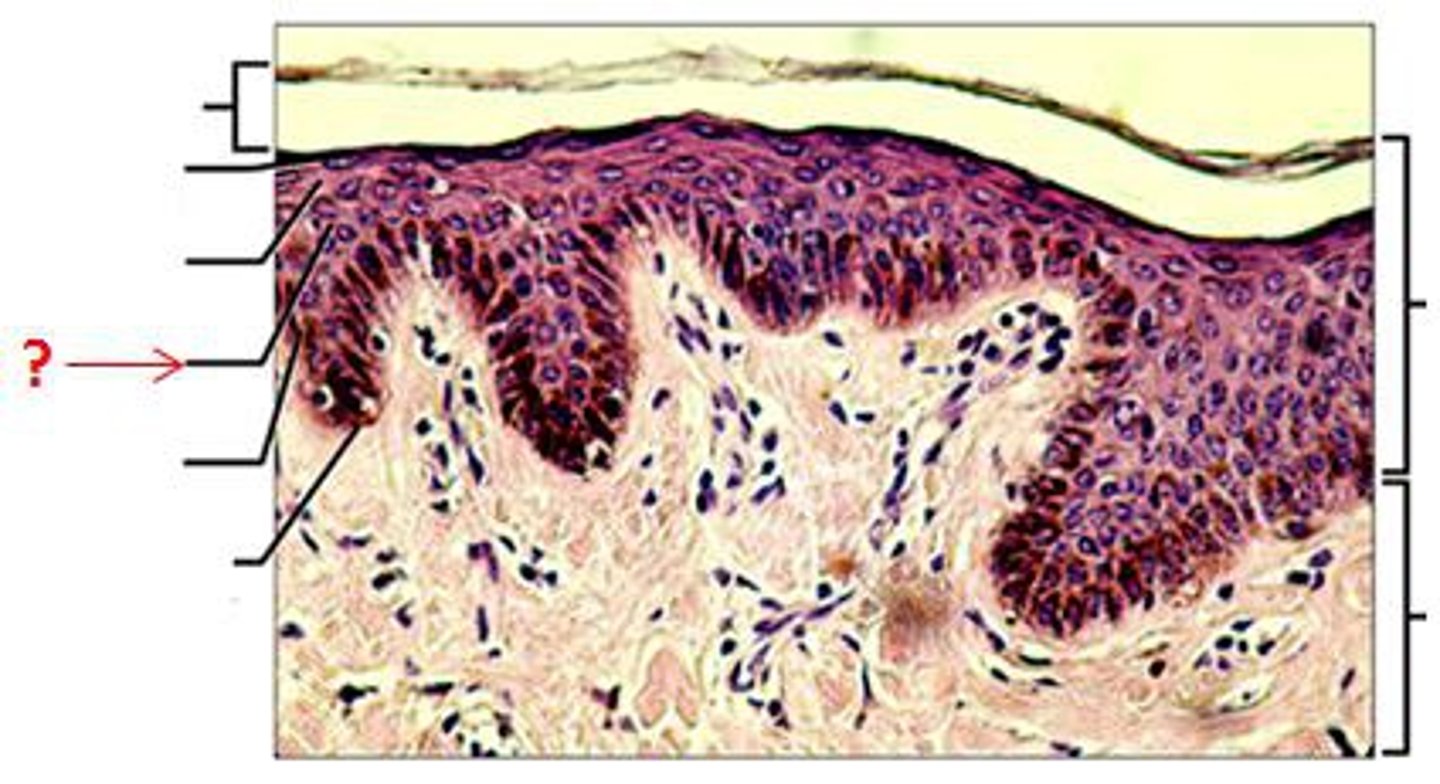

Epidermis

Outer layer of skin

stratum corneum

outermost layer of epidermis

stratum lucidum

Clear, transparent layer of the epidermis under the stratum corneum.

stratum granulosum

a layer of the epidermis that marks the transition between the deeper, metabolically active strata and the dead cells of the more superficial strata

stratum spinosum

stratum basale

the deepest layer of the epidermis consisting of stem cells capable of undergoing cell division to form new cells

Dermis

Inner layer of skin

papillary layer

outer layer of the dermis, directly beneath the epidermis; made of loose connective tissue

reticular layer

The deeper layer of the dermis that supplies the skin with oxygen and nutrients; made of dense irregular connective tissue

dermal papillae

a fingerlike projection of the dermis that may contain blood capillaries or Meissner corpuscles (of touch)